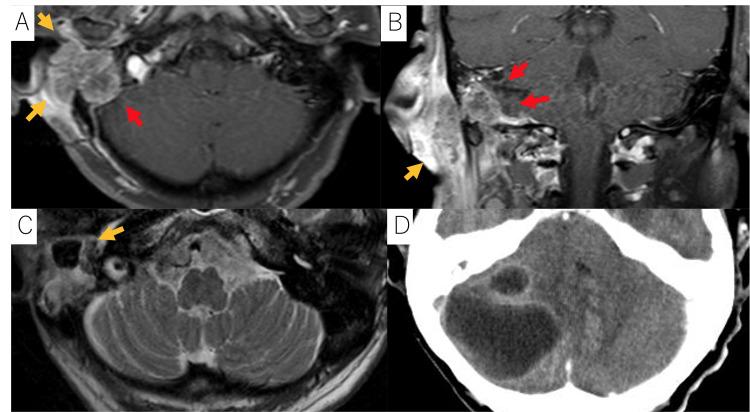

一名65岁女性,有斑块状银屑病和急性呼吸窘迫综合征病史,表现为右外耳道疼痛,被诊断出患有右EACC,EACC充满了右耳道,并侵犯了耳后皮肤、右乙状窦和硬脑膜(图1A、1B)。

放疗后不久,患者右耳出现持续性耳漏。放疗四年后还出现了慢性耳后皮肤瘘。定期随访增强磁共振成像(MRI)和PET-CT,以监测疾病进展和治疗效果。初次治疗七年后,MRI显示右颞骨破坏,提示骨放射性坏死(图1C)。治疗后八年,患者出现发烧和呕吐。CT扫描显示右小脑有一个低密度区域的环状增强病变,与最大直径为43毫米的小脑脓肿一致(图1D)。MRI T1加权成像显示低信号强度,而T2加权成像显示高信号强度。实验室检测表明,白细胞计数升高(11800/µL),C反应蛋白水平升高(1.98mg/dL)。脓肿采用引流和抗生素治疗。脓肿内鉴定出鸟肠球菌、棒杆菌、铜绿假单胞菌、帝汶类芽孢杆菌和脆弱拟杆菌。给药头孢曲松、甲硝唑和利奈唑胺。

图1 A、 B:磁共振成像(MRI)T1加权钆增强图像显示肿瘤(由黄色箭头和红色箭头表示)。此外,图像显示肿瘤侵入右乙状窦和硬脑膜(由红色箭头表示)。根据改良的匹兹堡分类法,该肿瘤被归类为T4。无颈部淋巴结转移或远处转移。C:MRI T2加权图像显示右颞骨破坏,在放射治疗(RT)后七年观察到(由黄色箭头表示)。D:计算机断层扫描(CT)显示右小脑有一个低密度区域的环状增强病变,与放疗后8年出现的小脑脓肿一致。脓肿的最大尺寸为43毫米。通过引流和抗生素治疗进行了治疗。患者没有复发或随后形成脑脓肿